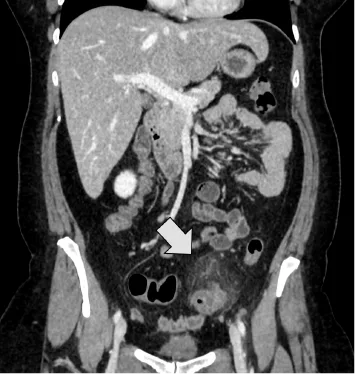

L’avenir, déjà présent sur les machines de dernière génération, est la reconstruction itérative dans les 3 directions de l’espace ; encore un peu longue en temps de calcul compte tenu de la complexité des algorithmes utilisés (40 à 1 heure par examen en 2014), cette technique permet de diminuer la dose à un niveau tel que la dose d’un scanner abdominal devient équivalent à celle d’un ASP de face (Radiographie de l’Abdomen sans préparation) soit environ 1 mS pour un passage (Fig. 3).

Figure 3. Reconstruction coronale de 2 images acquises chez le même patient atteint d’une sigmoïdite diverticulaire (flèche). A. Examen réalisé à plein dose soit 10 mSv. Images du Pr Pierre Alexandre Poletti, HUG

B. Examen réalisé à 1,2mSV (30 mAs, reconstruction itérative de type ASIR 40 %).

C. Même image mais reconstruite avec une itération appelée VEO (40 minutes de calculs nécessaire).